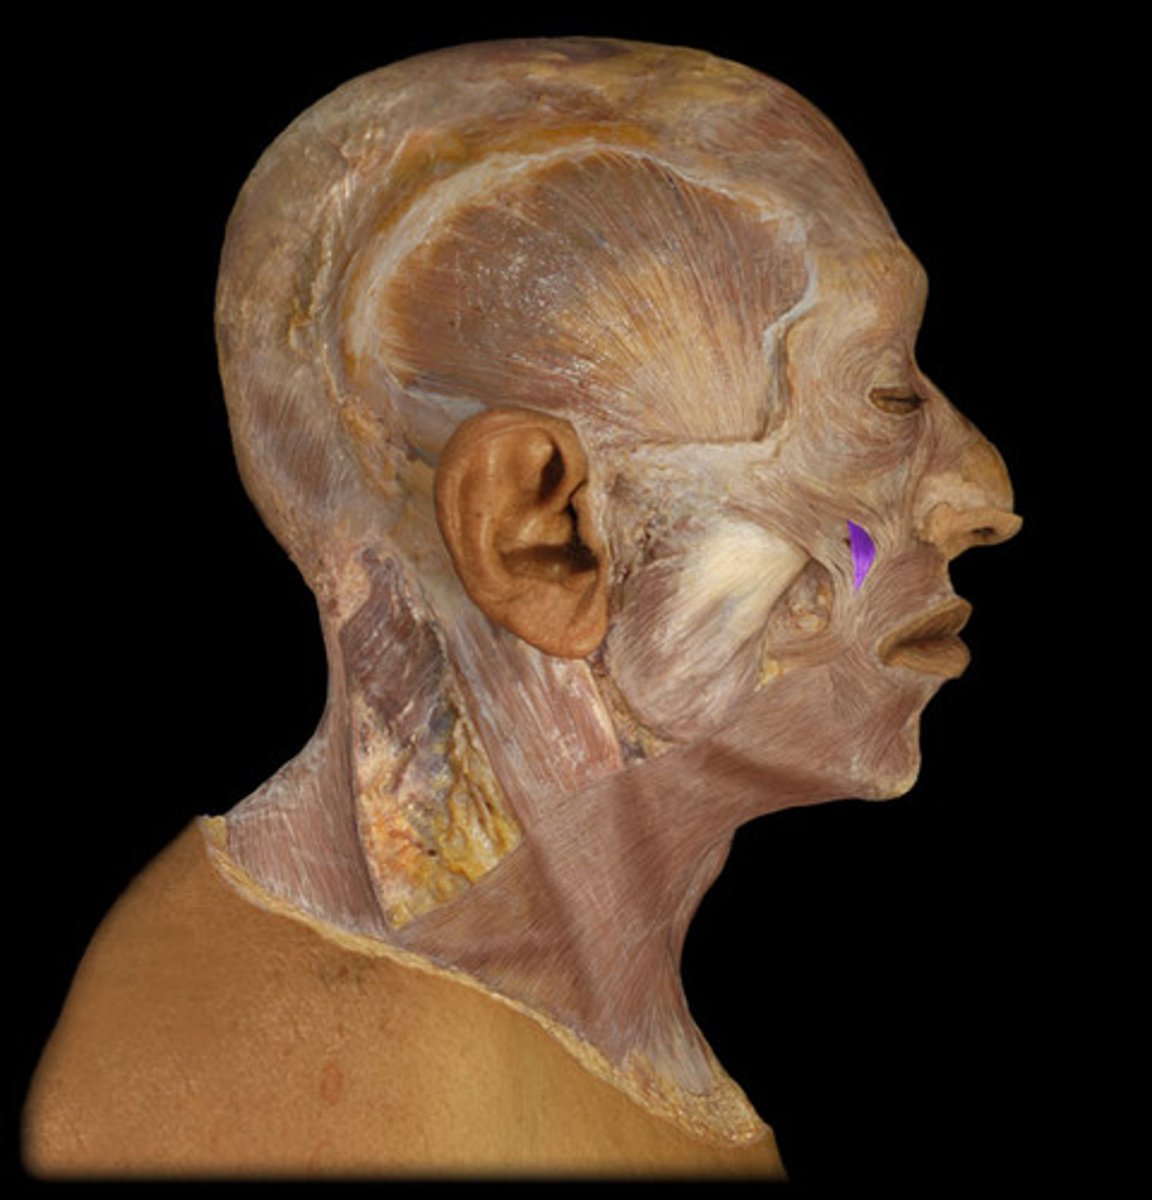

Zygomaticus major m.

Origin: Zygomatic arch

Insertion: Corner of mouth

Action: Elevate (smile)

Zygomaticus minor m.

Origin: Zygomatic arch

Insertion: Corner of mouth

Action: Elevate (smile)